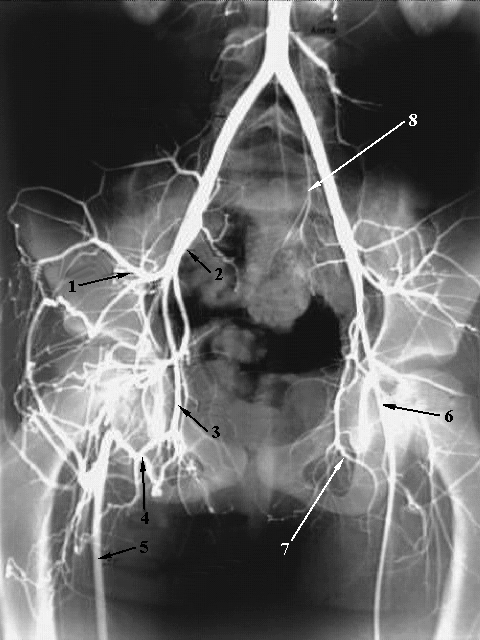

Lower Limbs: Femoral Artery Occlusion

1. Superior gluteal artery

2. Internal and external Iliac artery (superimposed)

3. Obturator artery

4. Medial femoral circumflex artery

5. Right femoral artery

6. Left femoral artery

7. Obturator artery

8. Lateral sacral artery